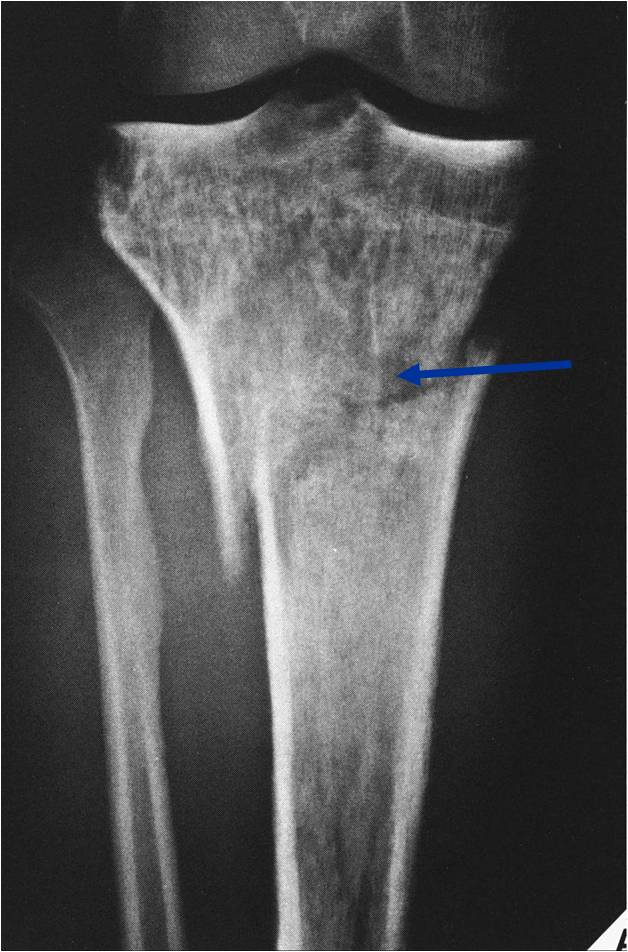

Permeative Lesion of Proximal Tibia with Pathological Fracture

- Permeative or moth eaten bone destruction (55%)

- Geographic (11%); Blow out (1%); Blastic (2%); Normal XR (5%)

- Metadiaphysis (75%)

- Periosteal reaction—may look benign